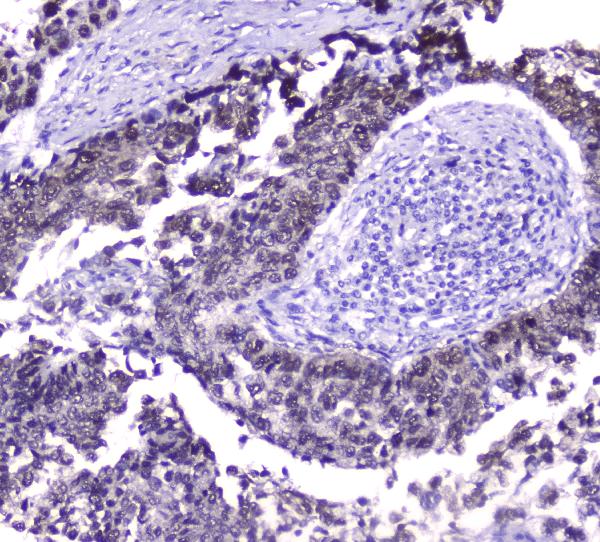

IHC analysis of HSP70 using anti-HSP70 antibody (M00949-2).

HSP70 was detected in a paraffin-embedded section of human lung cancer tissue. The tissue section was incubated with mouse anti-HSP70 Antibody (M00949-2) at a dilution of 1:200 and developed using HRP Conjugated mouse IgG Super Vision Assay Kit (Catalog # SV0001) with DAB (Catalog # AR1027) as the chromogen.